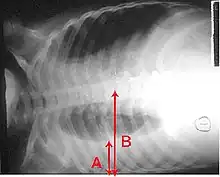

A chest radiograph is frequently used in diagnosis.[23] In people with mild disease, imaging is needed only in those with potential complications, those not having improved with treatment, or those in which the cause is uncertain.[23][67] If a person is sufficiently sick to require hospitalization, a chest radiograph is recommended.[67] Findings do not always match the severity of disease and do not reliably separate between bacterial and viral infection.[23]

X-ray presentations of pneumonia may be classified as lobar pneumonia, bronchopneumonia, lobular pneumonia, and interstitial pneumonia.[73] Bacterial, community-acquired pneumonia classically show lung consolidation of one lung segmental lobe, which is known as lobar pneumonia.[41] However, findings may vary, and other patterns are common in other types of pneumonia.[41] Aspiration pneumonia may present with bilateral opacities primarily in the bases of the lungs and on the right side.[41] Radiographs of viral pneumonia may appear normal, appear hyper-inflated, have bilateral patchy areas, or present similar to bacterial pneumonia with lobar consolidation.[41] Radiologic findings may not be present in the early stages of the disease, especially in the presence of dehydration, or may be difficult to interpret in the obese or those with a history of lung disease.[24] Complications such as pleural effusion may also be found on chest radiographs. Laterolateral chest radiographs can increase the diagnostic accuracy of lung consolidation and pleural effusion.[40]